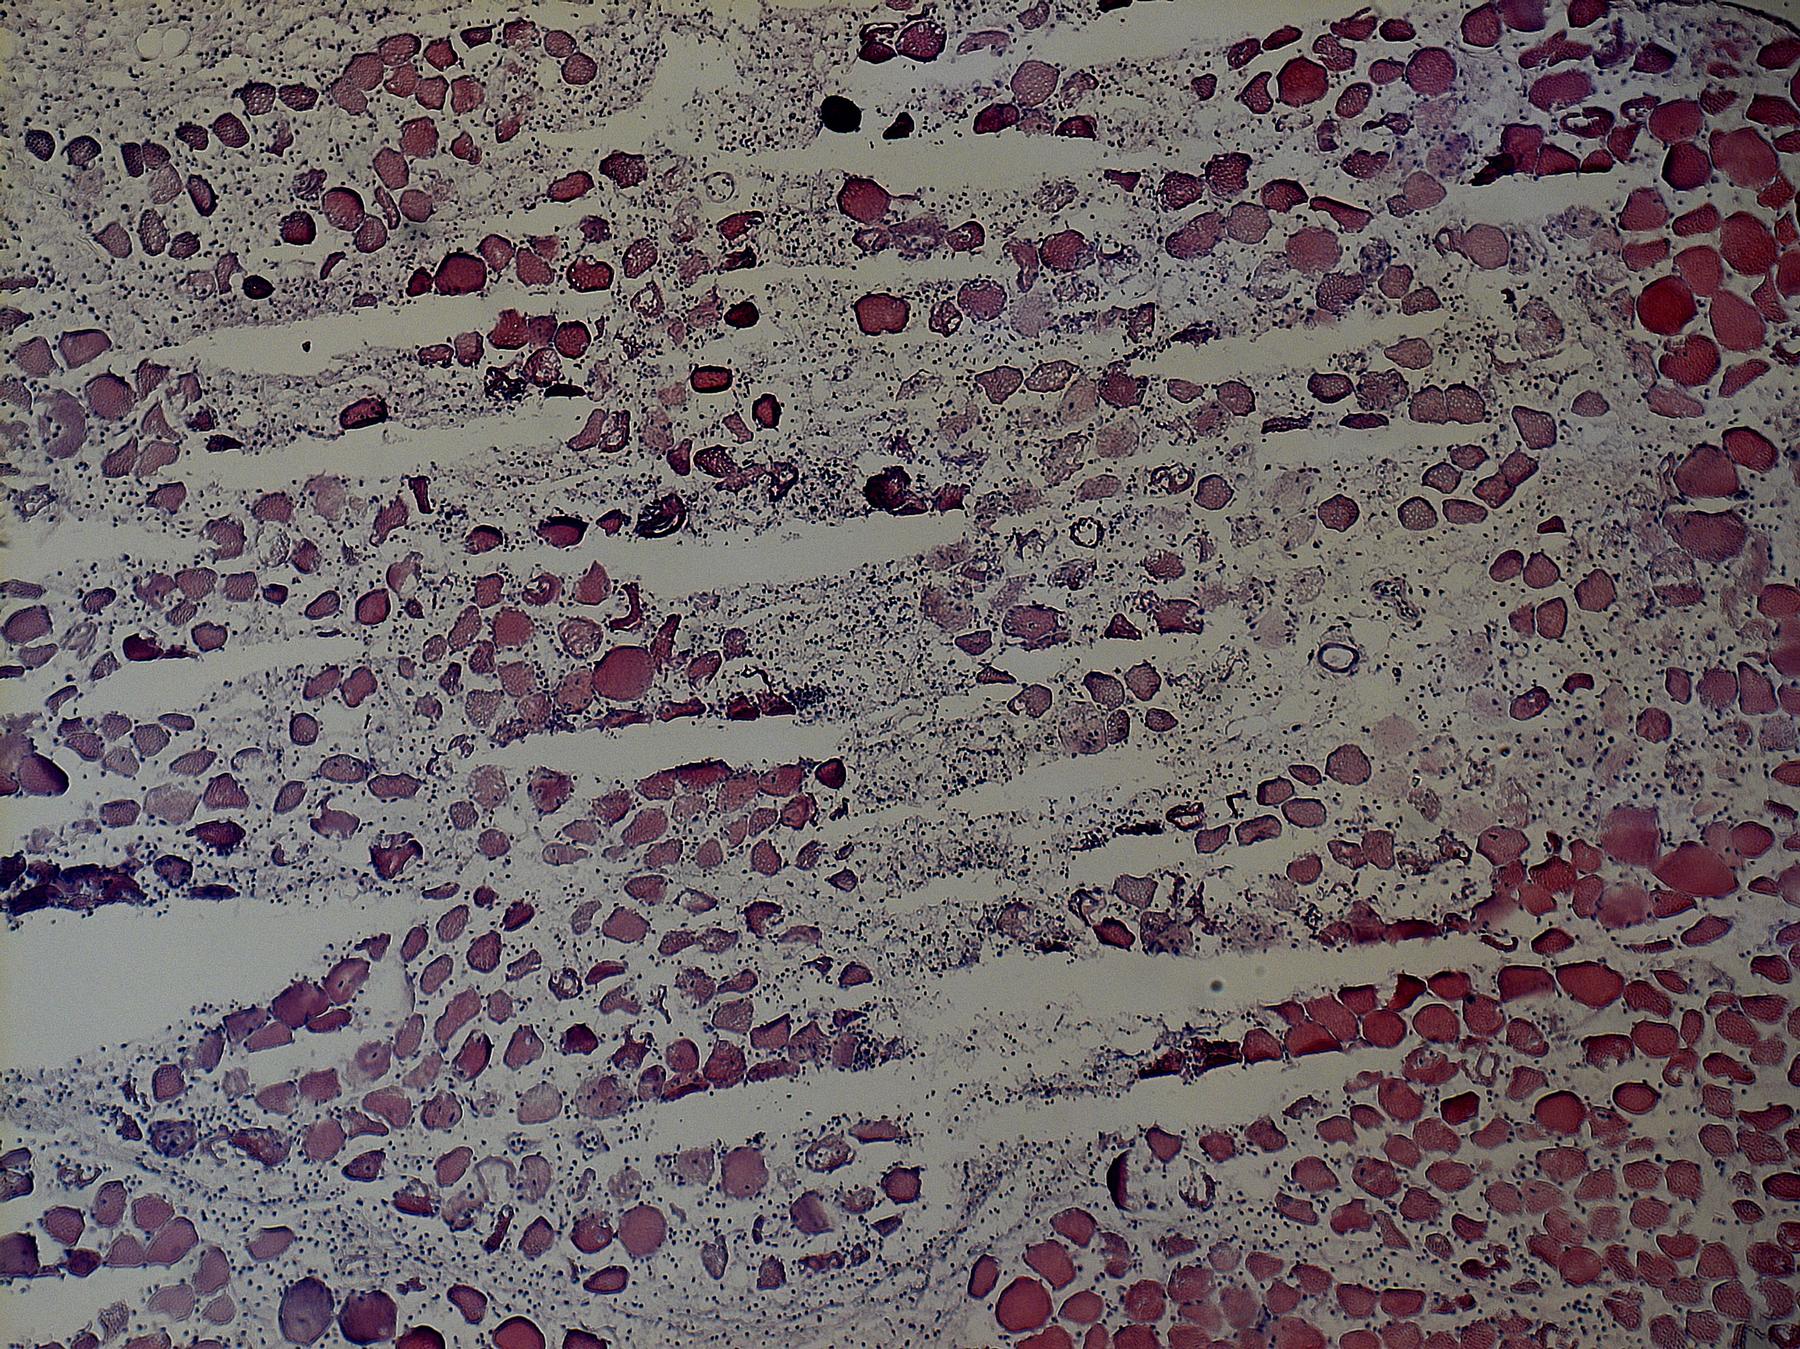

Die Akut-Diagnostik umfasst eine ausführlichen Anamnese mit Erfassung ggf. von körperlichem Training, Noxen und Toxinen, inklusive der Arbeitsplatzanamnese, und die klinische Untersuchung. Es folgt ein labortechnisches Work-up mit CK-, und Myoglobin-Bestimmung mit (insbesondere bei wiederholter Rhabdomyolyse) Gen-Exom-Analyse für „Rhabdomyolyse-assoziierte“ Genvarianten (z.B. CPT-2, PYGM, LIPIN1, RYR1, u.a.). Ergänzend erfolgt ein Muskel-MR und der Elektrophysiologie. Eine Muskelbiopsie kann im Abstand von ca. 4-8 Wochen erfolgen, nicht zum Akutzeitpunkt. Ergänzend wird eine kardiopulmonale Diagnostik durchgeführt.